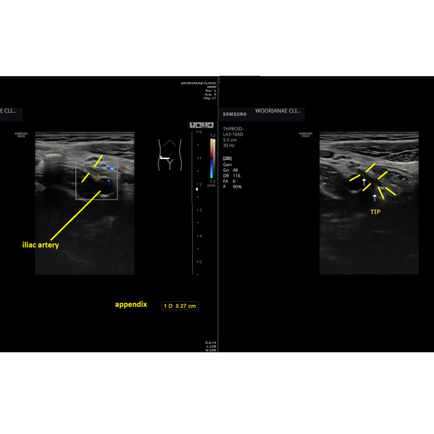

하복부, 골반 초음파; 난소종양

17시간 전

1분 분량